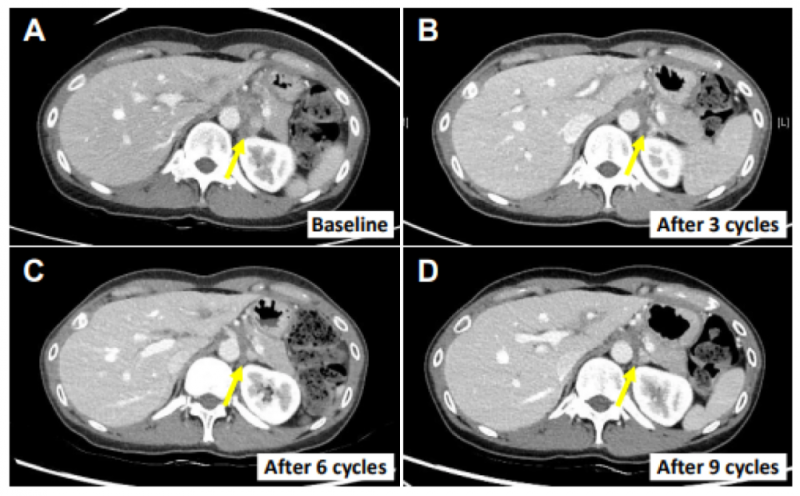

1、患者E0107(40岁女性):因胆囊炎行胆囊切除术后,确诊为胆囊癌伴腹膜转移,既往接受过吉西他滨、顺铂、5-氟尿嘧啶(5-FU)、伊立替康脂质体(onivyde®)+亚叶酸钙等多线化疗。在接受SMT-NK联合帕博利珠单抗治疗后,转移性淋巴结缩小82.3%(图3A-D),且初始治疗后18个月仍无进展。

▼患者E0107的左肾下淋巴结治疗前后对比

▲图源“Cancers”,版权归原作者所有,如无意中侵犯了知识产权,请联系我们删除